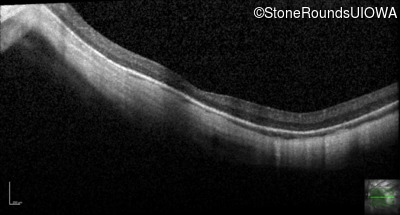

Optical Coherence Tomography - Right - 10/100 -2

Exemplar / OCT Stack

Optical Coherence Tomography - Left - 10/100 -2